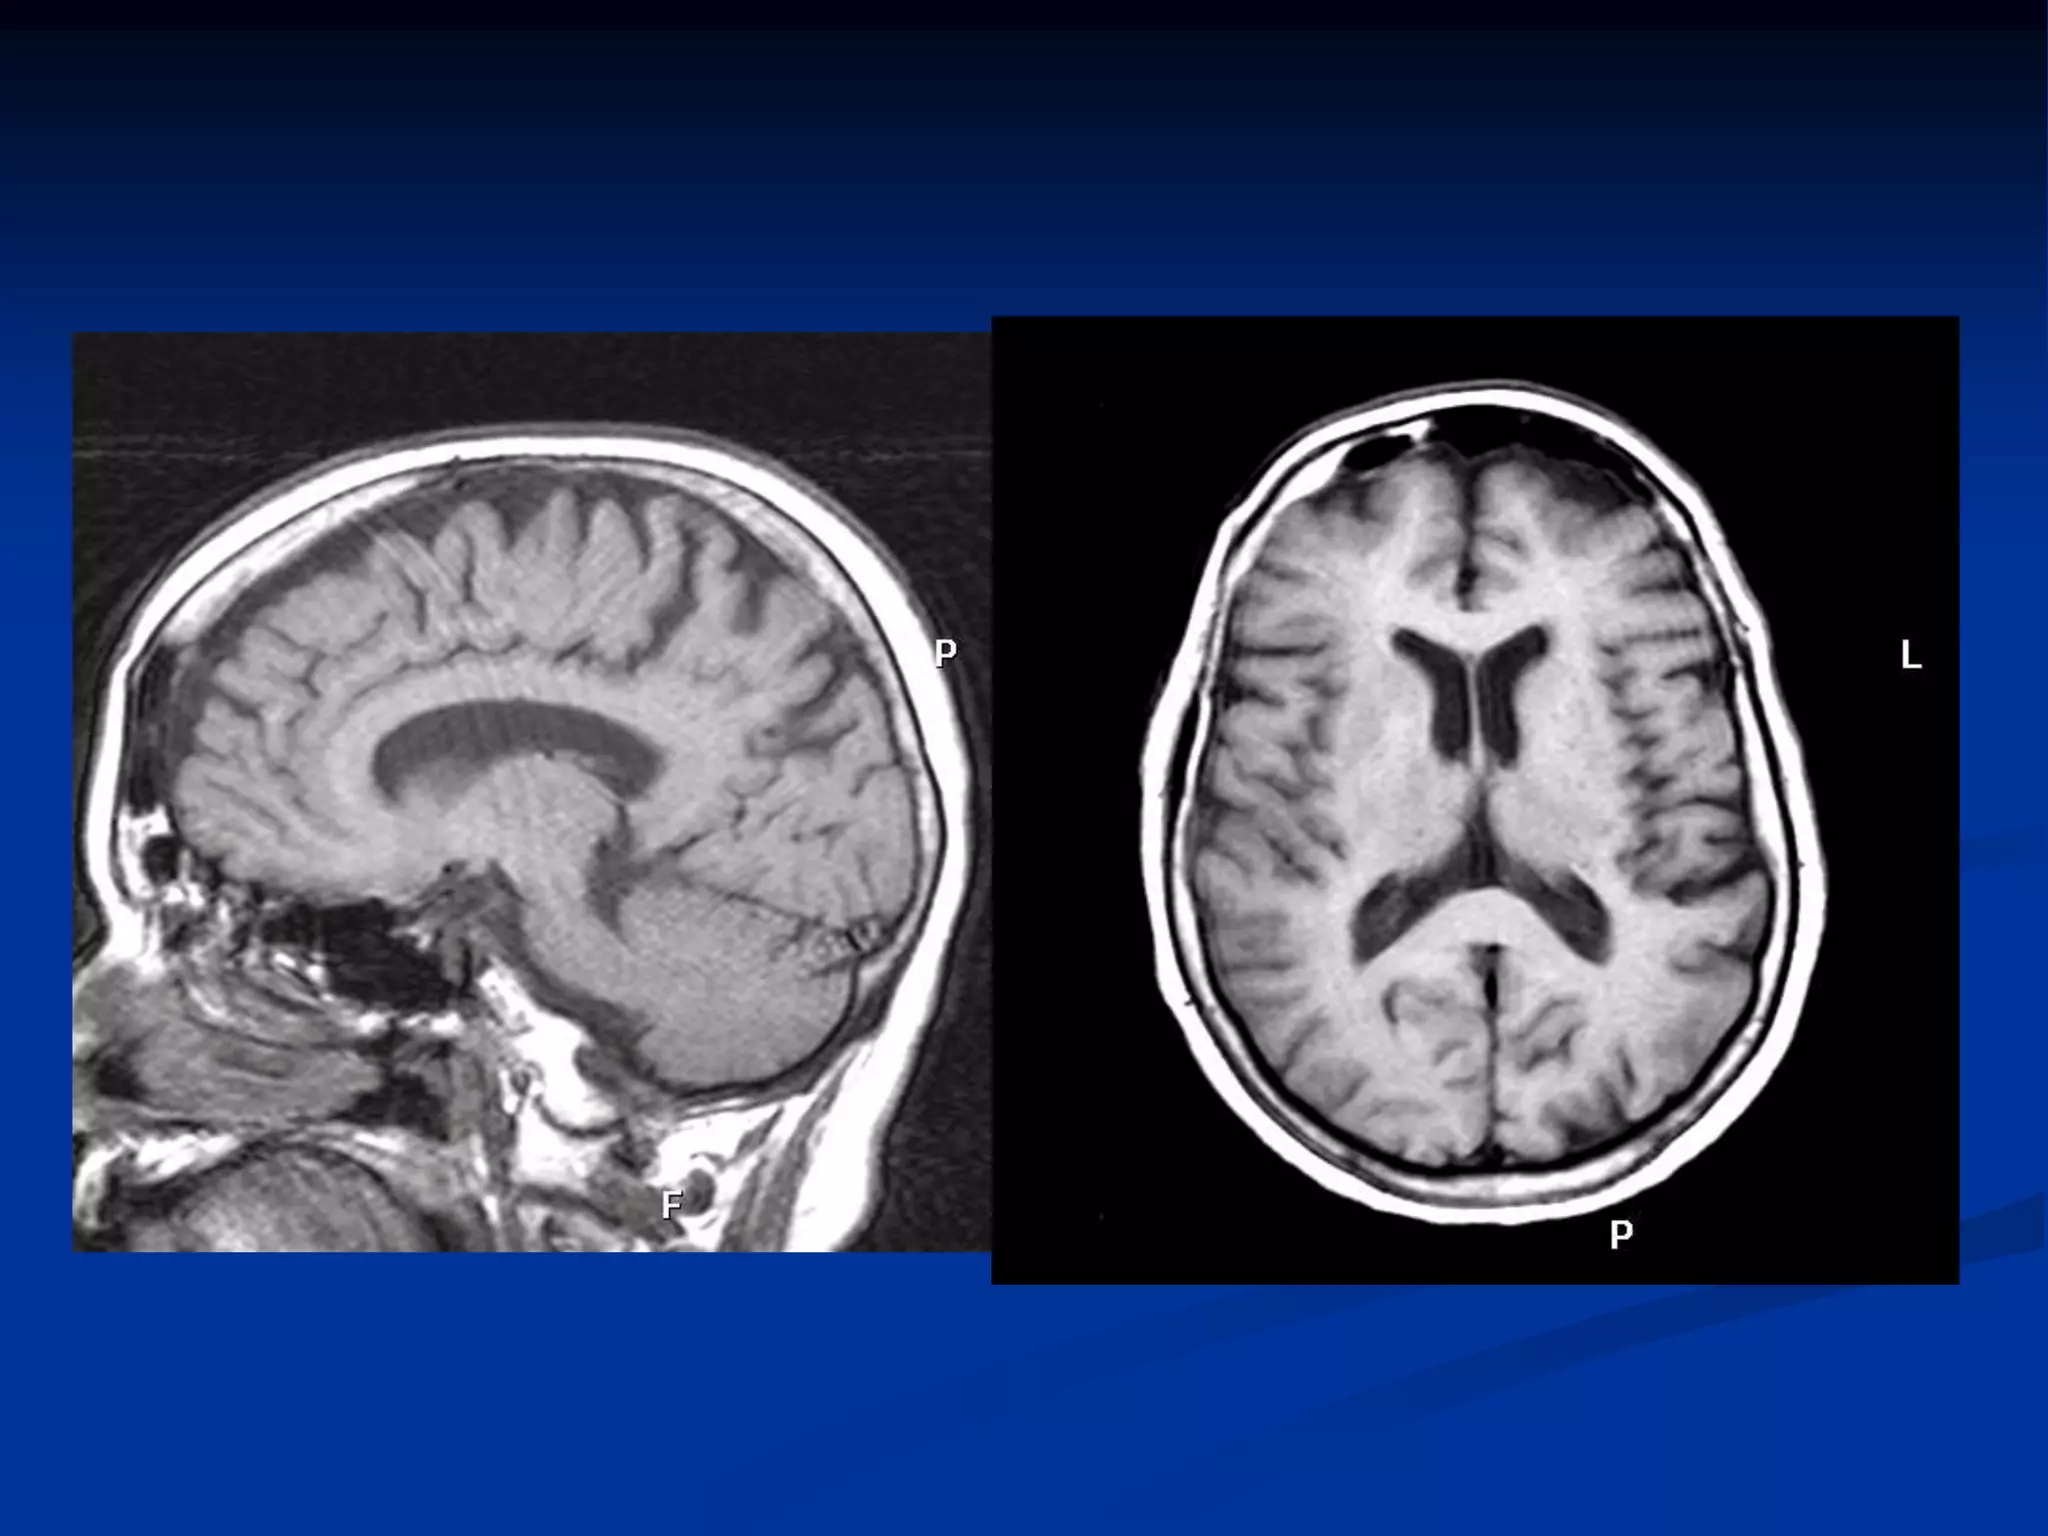

Potenciación en T1

   Para una potenciación en T1 el TR tiene que ser

corto (400-600 ms) para resaltar diferencias en la

señal de relajación T1 en los tejidos. (rapidez de

la recuperación de la mag. Long.).

   El TE debe ser corto(30ms) para evitar que se

manifieste el efecto T2.

   Cuanto mas corto el T1 mas intensa la señal.

ESTA SECUENCIA SE USA

PARA EVALUAR ANATOMIA